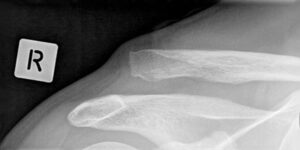

X-ray image of an AC dislocation.